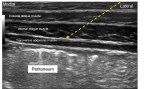

- Ilioinguinal/Iliohypogastric block with Ultrasound Guidance